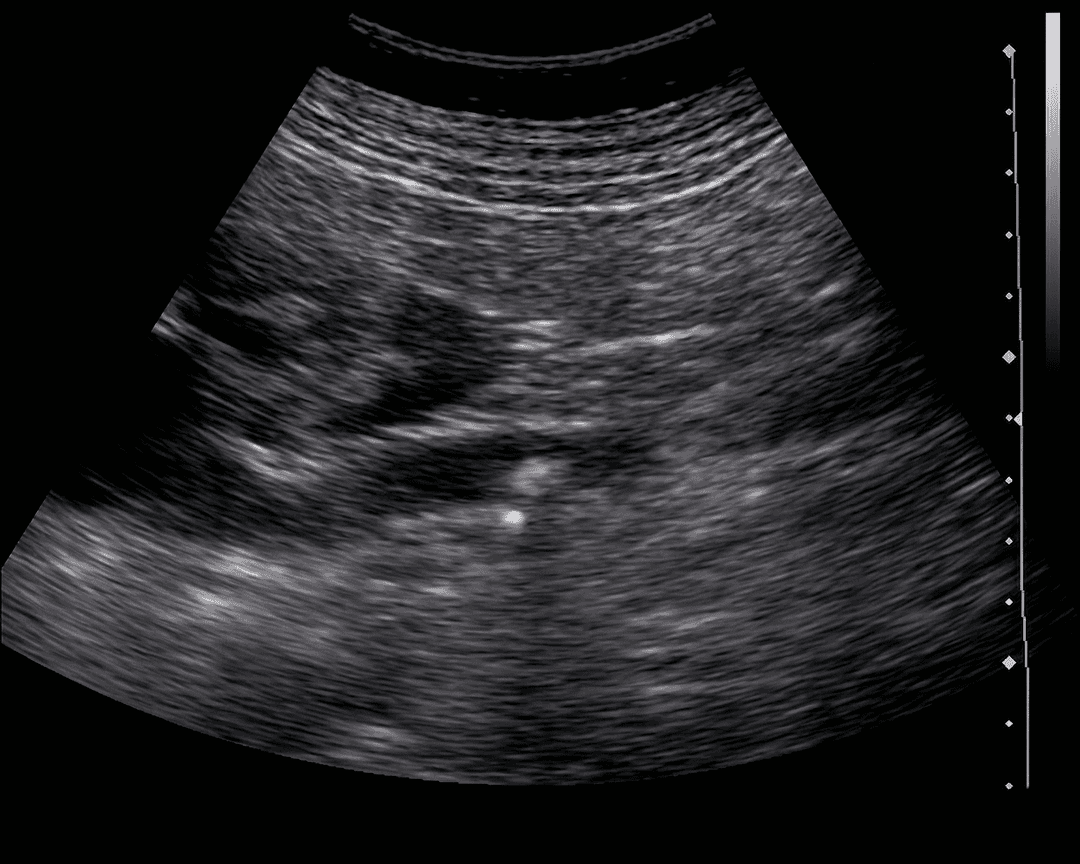

Ultrasonido renal realizado con transductor convexo que demuestra un foco hiperecogénico compatible con litiasis en el sistema colector, asociado a sombra acústica posterior, hallazgo característico de cálculos calcificados. Se observa además dilatación retrógrada del sistema pielocalicial (hidronefrosis), lo que sugiere obstrucción urinaria secundaria. El ultrasonido constituye una modalidad inicial ampliamente utilizada en la evaluación de urolitiasis, particularmente en pacientes pediátricos y embarazadas, permitiendo identificar tanto el cálculo como las repercusiones obstructivas sobre el riñón.